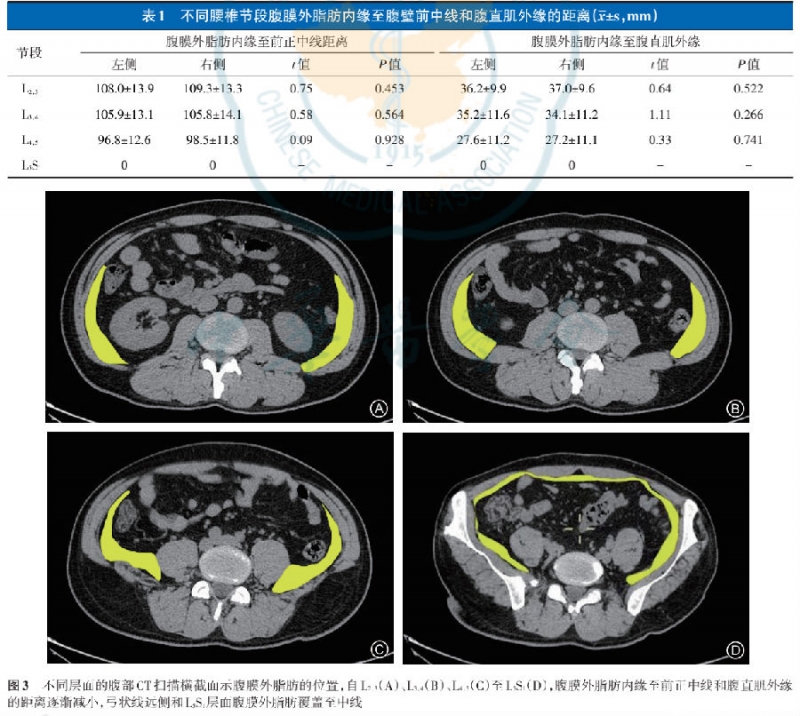

影像学观察及测量

腹部CT观察提示L4-L5横断面位于耻骨联合与脐中上1/3水平处;L5-S1位于肚脐和耻骨联合中下1/3水平处;L3-L4大致位于脐平面,L2-L3位于脐头侧;在L2~L5节段腹部CT横截面上腹膜外脂肪内缘至腹壁前中线和腹直肌外缘的距离如所示。L5-S1水平处腹直肌深面存在腹膜外脂肪;自L2-3至L4-5,腹膜外脂肪内缘至腹壁前中线和腹直肌外缘的距离均逐渐变小,且左右两侧距离无明显差异(表1,图3)。